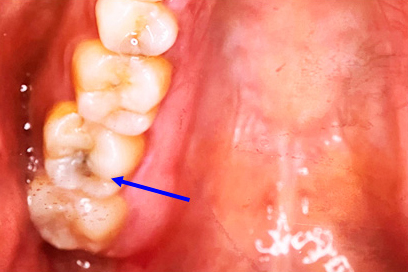

奥歯のジルコニア

| 年齢・性別 | 22歳・男性 |

|---|---|

| 主訴・治療部位 | 他院で虫歯治療 詰め物の治療が必要と判断を受けたが、自費診療の費用が高価で治療を断念 インターネットで当院を知りご来院 右上6番、右上4番 |

| 治療費用 | 合計:88,000円 ジルコニア:44,000円×2 (2023年1月現在) |

| 治療期間 | 約1ヵ月 |

| 治療内容 | 虫歯を除去し、型をとりました。 神経の近くまで虫歯になっていたため、神経の保護処置も行いました。 |

| リスク・副作用 | 虫歯が進行し、神経の治療になる可能性があります。 神経の近くまで削っているため、治療直後は敏感になり痛みが出る可能性があります。 かみ合わせの強い方は詰め物が取れてしまう可能性があります。 |

| 治療方針 | 治療必要な箇所は終了 親知らずは埋まっているが、痛みや腫れはないため、定期検診にて経過観察していきます。 |

| 担当者所見 | 歯周病検査は異常なし 虫歯リスクを下げるため、歯ブラシの他にフロスや歯間ブラシの併用を提案しました。 |